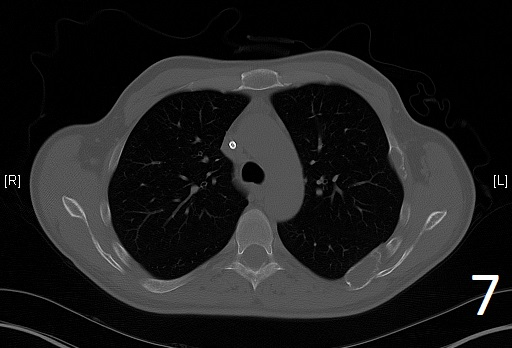

Fig. 7

Fig. 6-7. Axial CT reconstruction of the chest showing lytic and expansile lesion of the left scapula and ribs (polyostotic fibrous dysplasia).